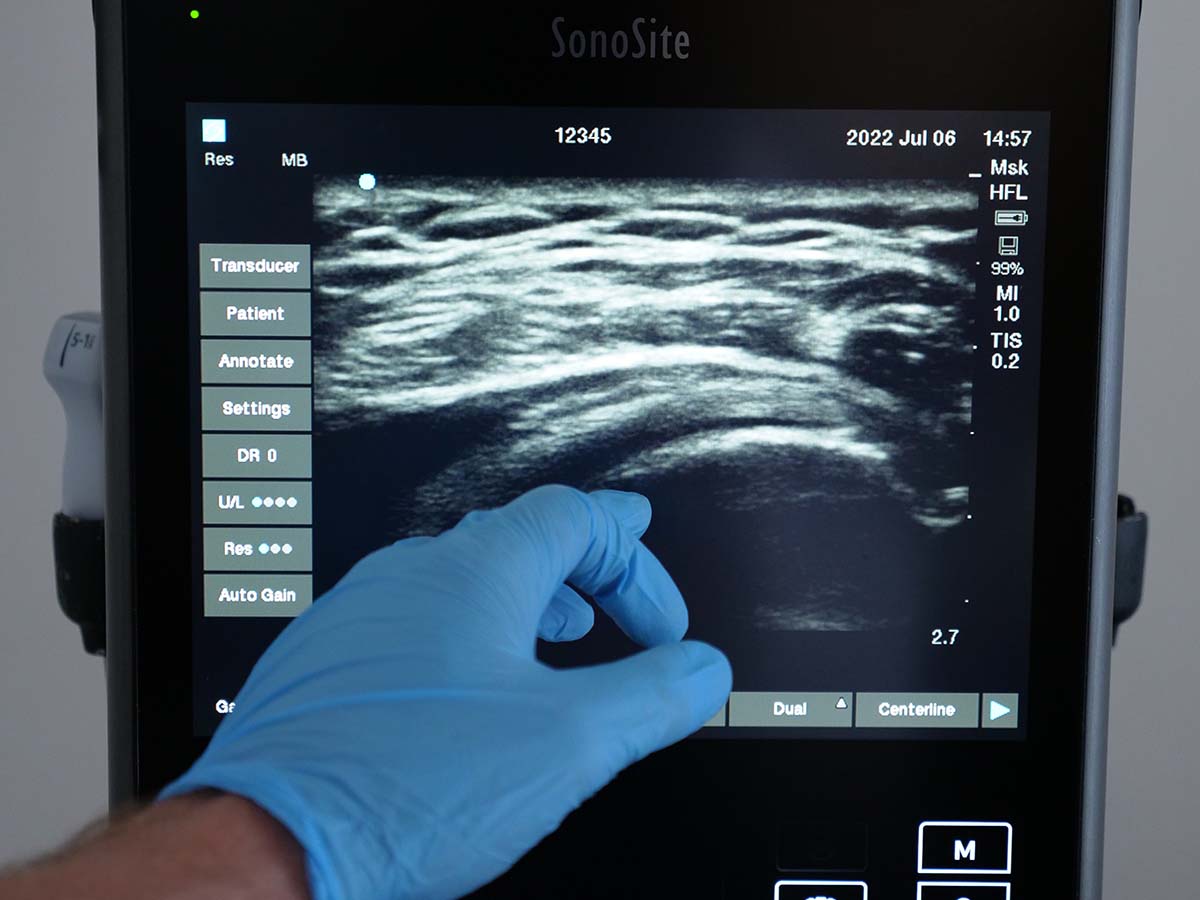

Through focused teaching and practical skill development, you’ll build confidence in image acquisition, optimisation, and interpretation for superficial structures. The module emphasises recognition of normal and abnormal appearances, common benign lesions such as lipomas and cysts, and key red flags for malignancy.

- Image acquisition, optimisation, and probe selection for superficial structures

- Artefact recognition and image interpretation

- Recognition of common benign soft tissue lesions: Lipomas, sebaceous cysts, ganglion cysts

You will have access to video materials covering the theoretical content. Didactic teaching will be combined with practical face-to-face sessions, where you will use a range of ultrasound systems to develop scanning skills on normal volunteers. Additionally, simulators will be used to practise imaging and identifying various abnormalities.